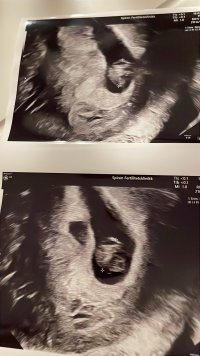

Her var lille økt fra 4 mm forrige tirsdag til 11 mm i dag12,7 millimeter her, og dette er IVF-baby, så vi vet på timen hvor gammel den er![]()

Så nydelig! Tenkte på deg når vi satt på de grønne stolene og ventetHer var lille økt fra 4 mm forrige tirsdag til 11 mm i dagJeg er 7+2 i dag og det stemte helt med IVF-datoen og målingen

Er 6+6 i dag, men fosteret var 0,5 mm så det svarer til 6+1 ca. Så vi får håpe at det er bra! Såg to sekker, men bare ett foster. I alle fall ett godt tegn med bankende hjerte, så får vi ta det deretter!Sååå fin! Ser ut som en bitteliten baby joVar på ny UL i dag